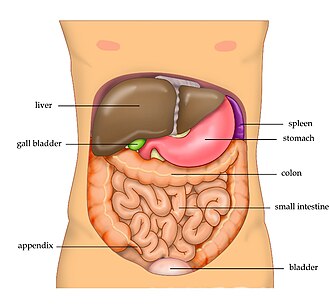

Abdominal cavity

large space between diaphragm and pelvis

Abdominal

between the chest and pelvis (abdomin)